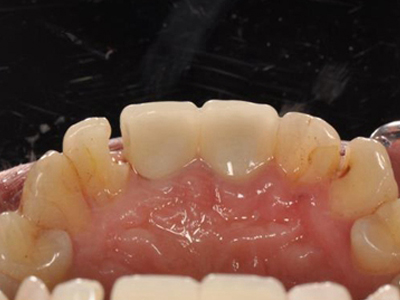

酸蚀症牙齿缺损有洞图

患酸蚀症时,牙齿可发生缺损,表现为牙列内侧有凹陷的坑洞形成,形状不规则,大小不一,坑洞处牙齿发黄,需积极控制病因,并进行充填修复治疗。